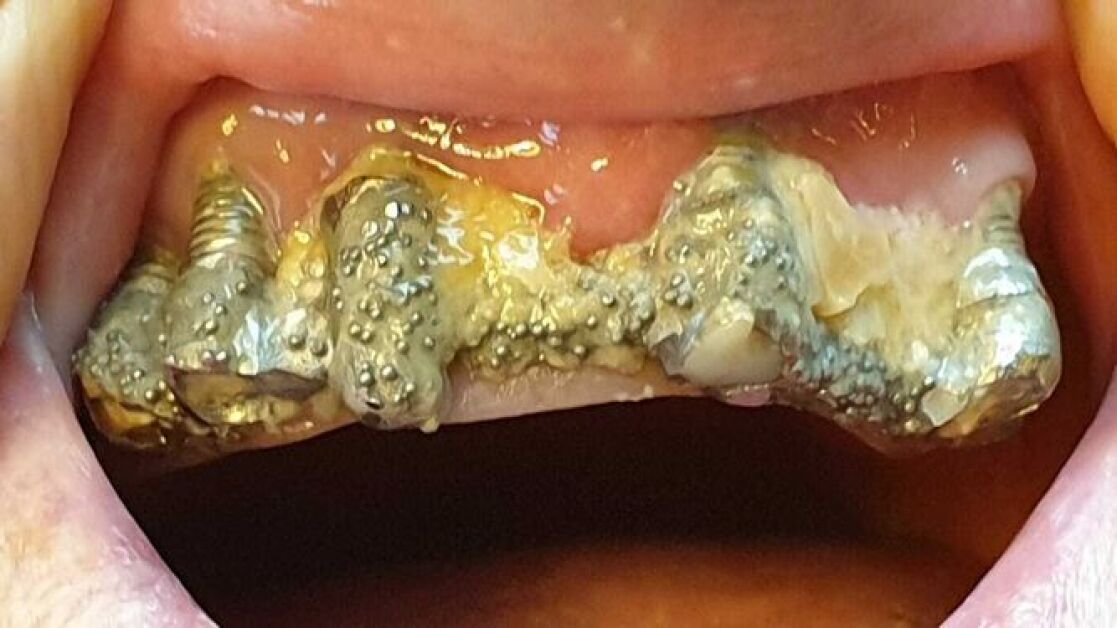

Cuenta que acudió por primera vez a la clínica en 2010 para colocarse implantes dentales en la parte superior de la boca, pero que el dentista le recomendó hacerlo también en la mandíbula inferior. Así, le extrajeron todos los dientes para susituirlos por piezas de porcelana, pero los implantes se deterioraban, se rompían y se infectaban constantemente. Por ello, le realizaron numerosas reparaciones y le recolocaron la prótesis varias veces, causándole lesiones en la boca.

Asegura que los arreglos que le hicieron en las coronas rotas a veces "duraban menos de una hora" y que, en 2016, tras más de 80 visitas al centro donde fue atendida por una decena de profesionales distintos, la clínica le comunicó que no se haría cargo de más reparaciones. A partir de entonces tendría que asumir el coste ella misma.